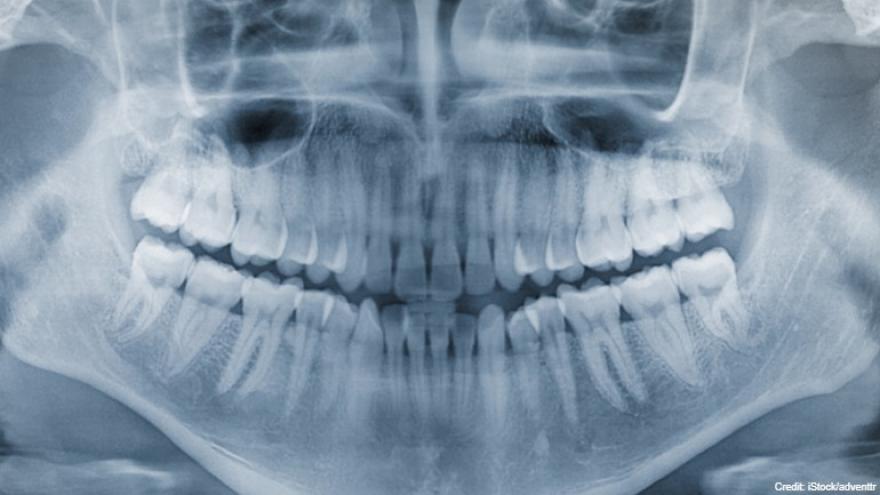

美国威斯康辛州61岁牙医查莫里多年来故意毁损患者的牙齿以赚取数百万美元,东窗事发后于本月10日被控5项医疗保健诈欺罪和2项患者治疗虚假陈述罪名。

检察官指出,查莫里经常故意鑽坏或毁损患者的牙齿,再向他们收取额外的治疗费,以修复他造成的伤害。查莫里年收入从2014年的140万美元、安装434个牙冠,激增到2015年年收入250万美元,安装1000多个牙冠。

检察官称查莫里2015年开始向患者施压,要求他们在受损牙齿上装不必要的牙冠。在装牙冠前查莫里会提供保险公司他故意损坏牙齿的X光片,以证明患者有必要进行牙冠手术。

查莫里从2016年至2019年期间,从牙冠手术赚取超过420万美元的费用,比同期威斯康辛州95%牙医做的牙冠手术还多。